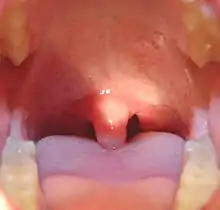

Uvula

The uvula, also known as the palatine uvula, is a conic projection from the back edge of the middle of the soft palate, composed of connective tissue containing a number of racemose glands, and some muscular fibers.[1][2] It also contains many serous glands, which produce thin saliva.[3] It is only found in human beings.[4]